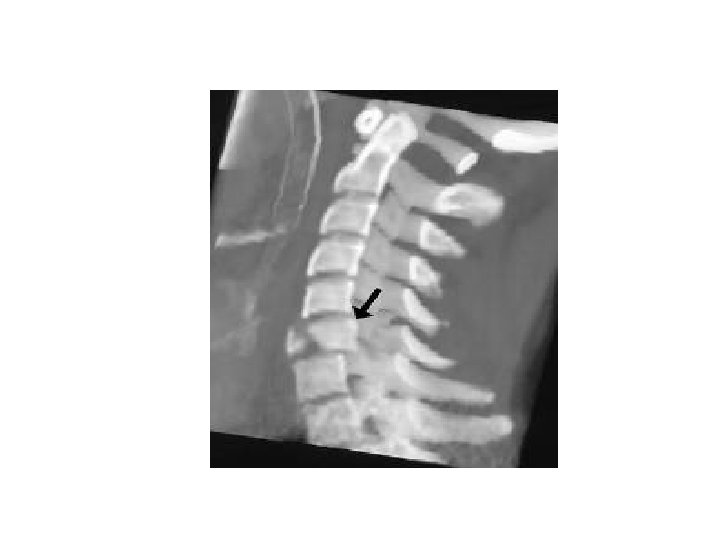

BURST FRACTURE • Fracture of C 3 -C 7 that results from axial compression • Spinal cord injury secondary to displacement of posterior fragments is common. • Mechanism – Axial compression • >25% loss of height of vertebral body • Stable • Needs CT or MRI